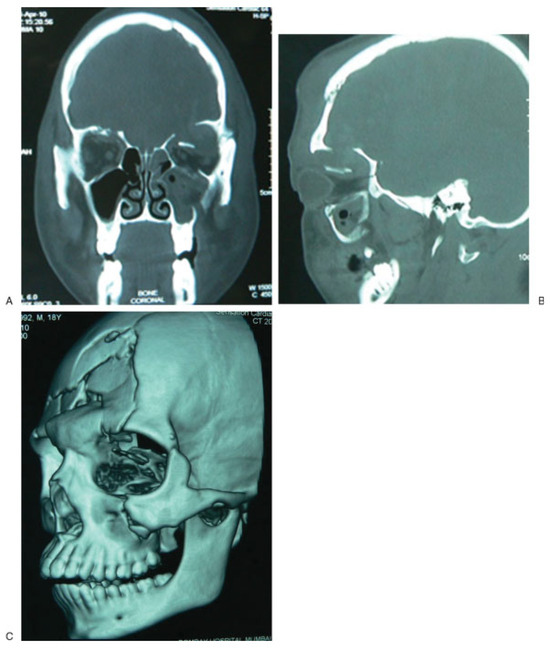

Titanium Mesh Reconstruction of Orbital Roof Fracture with Traumatic Encephalocele: A Case Report and Review of Literature

Case Report